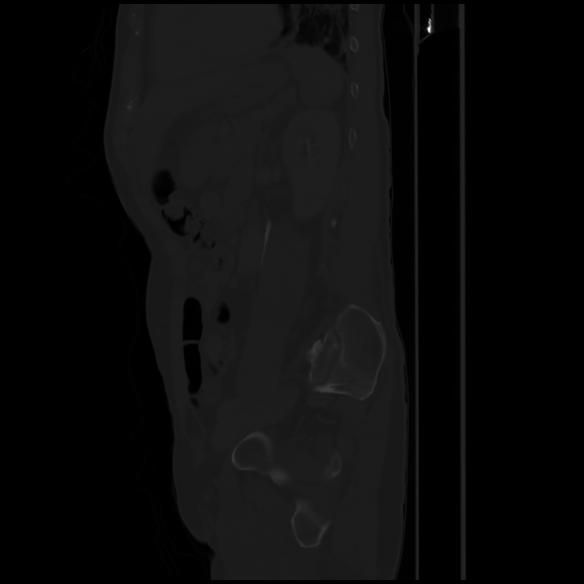

7 CUERPO,CE,Sagittal,3.000,CUERPO,Sagittal,